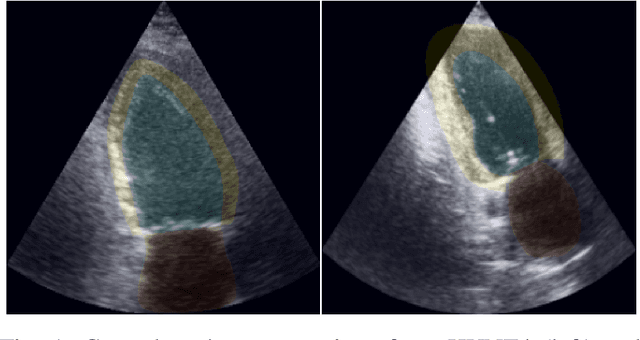

Abstract:Automatic estimation of cardiac ultrasound image quality can be beneficial for guiding operators and ensuring the accuracy of clinical measurements. Previous work often fails to distinguish the view correctness of the echocardiogram from the image quality. Additionally, previous studies only provide a global image quality value, which limits their practical utility. In this work, we developed and compared three methods to estimate image quality: 1) classic pixel-based metrics like the generalized contrast-to-noise ratio (gCNR) on myocardial segments as region of interest and left ventricle lumen as background, obtained using a U-Net segmentation 2) local image coherence derived from a U-Net model that predicts coherence from B-Mode images 3) a deep convolutional network that predicts the quality of each region directly in an end-to-end fashion. We evaluate each method against manual regional image quality annotations by three experienced cardiologists. The results indicate poor performance of the gCNR metric, with Spearman correlation to the annotations of \r{ho} = 0.24. The end-to-end learning model obtains the best result, \r{ho} = 0.69, comparable to the inter-observer correlation, \r{ho} = 0.63. Finally, the coherence-based method, with \r{ho} = 0.58, outperformed the classical metrics and is more generic than the end-to-end approach.